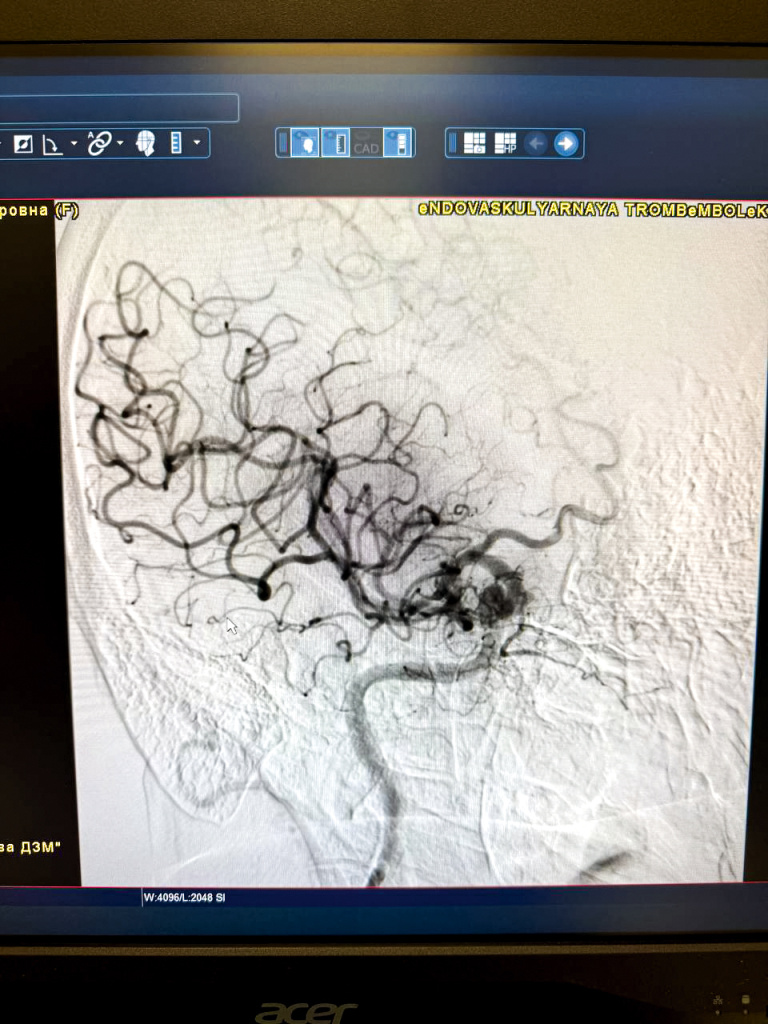

С учётом отсутствия противопоказаний женщине выполнили тромболизис – медикаментозное лечение ишемического инсульта, при котором вводится специальный препарат, растворяющий тромб и восстанавливающий кровоток. Совместно с неврологической службой к лечению больной подключились и эндоваскулярные хирурги. «Учитывая уже известную локализацию тромба в самом начале правой средней мозговой артерии (этот сосуд питает всё полушарие головного мозга), мы сразу подвели необходимый специализированный эндоваскулярный инструмент к проблемному сосуду и аспирационной методикой с первого прохода извлекли главного виновника инсульта – тромбоэмбол размером 3–4 миллиметра», – прокомментировал заведующий отделением рентгенэндоваскулярной хирургии Городской клинической больницы имени В. В. Вересаева Михаил Струценко.